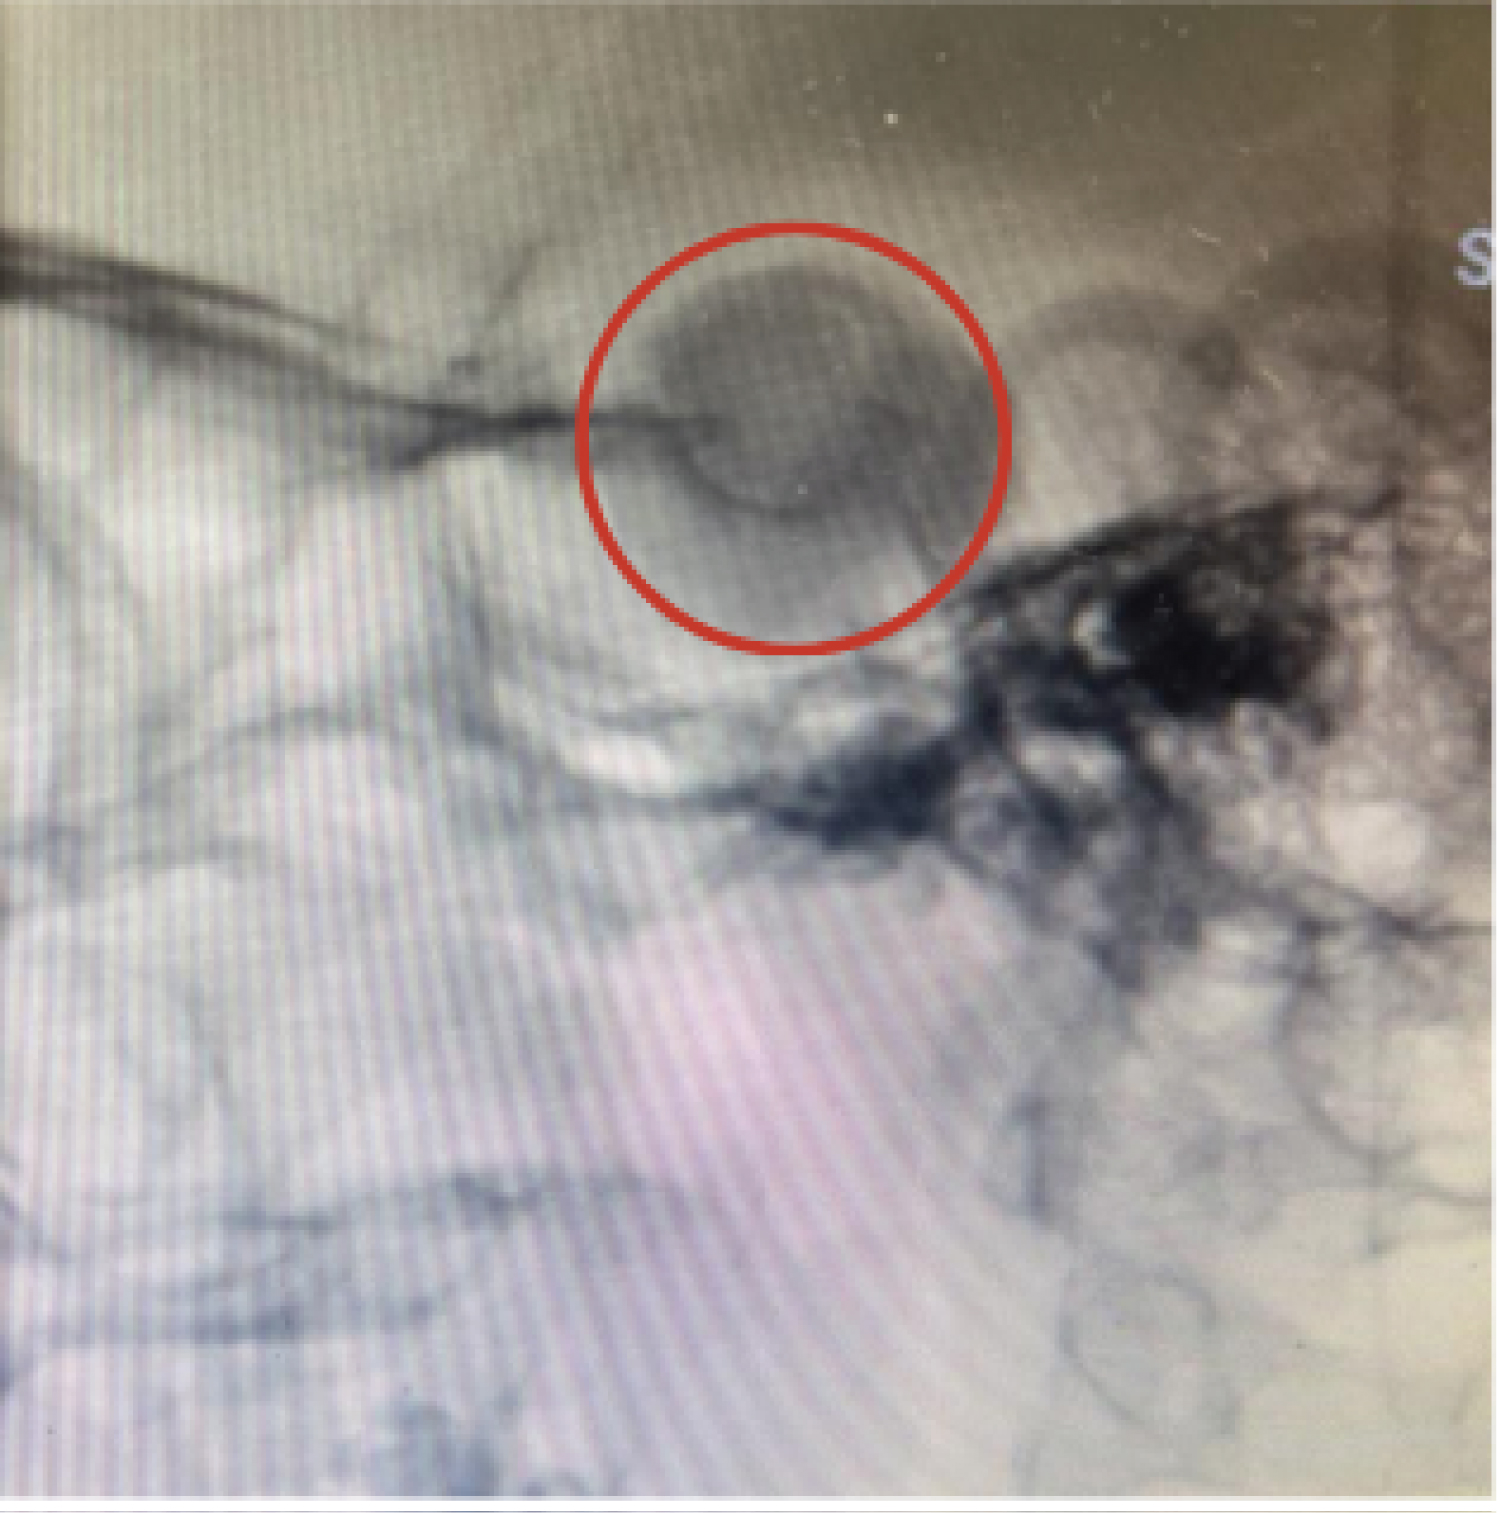

Positioned the 6F introducer sheath in the right femoral artery using the technique described by Seldinger; systemic heparinization performed with 5,000 IU of venous heparin. Positioned the 6F guide catheter in the left carotid artery with the aid of a hydrophilic guide wire of 0.035-150 cm; in angiography series, a large partially thrombosed aneurysm in the left internal carotid artery in the cavernous segment with a fistulous component was documented (Figure 3), along with dilation of the ophthalmic veins. Microcatheterization of the C5 segment of the ICA was performed assisted by a 0.14 micro-guide wire, reaching the superior ophthalmic vein through the cavernous sinus (Figure 4). Ten coils were then placed, with a satisfactory angiographic result (Figure 5). At the time of hospital discharge, clinical improvement was already reported, and at the 30-day follow-up appointment, the patient was asymptomatic. In the third month, during the outpatient follow-up, symptom recurrence was observed, and on the control angiography, fistula recurrence with coil migration within the cavernous sinus was evident (Figure 6). This case report was documented with the patient's signature on the informed consent form.

Figure 6: Angiography of the left internal carotid artery (LICA) arterial phase in anteroposterior (AP) demonstrating recurrences of the carotid-cavernous fistula (CCF) (green arrow) in Figure B. Coil migration within the cavernous sinus by comparing the red circle in Figure A with the red circle in Figure B. View Figure 6